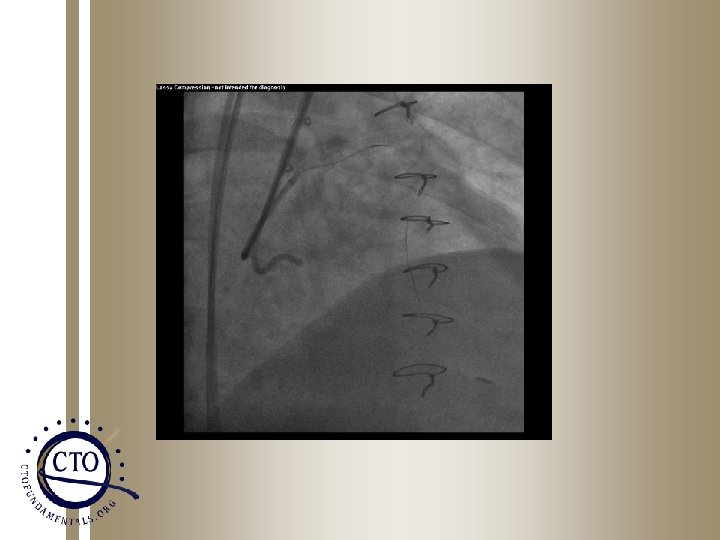

Snares • Ensnare – Usually 27 mm or 30 mm snares – Wire brought retrograde into aorta and snare used to bring wire into antegrade system and then externalize